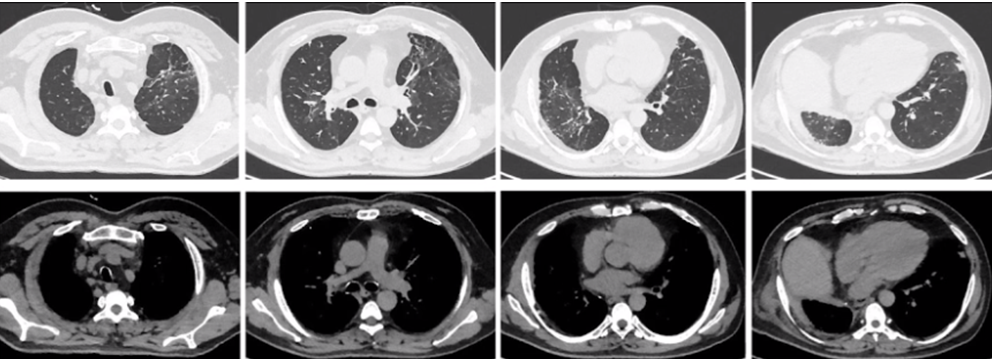

4月20日胸部CT:左上肺大实变渗出影(图8)

图片

图8  患者胸部CT(2020年4月20日)